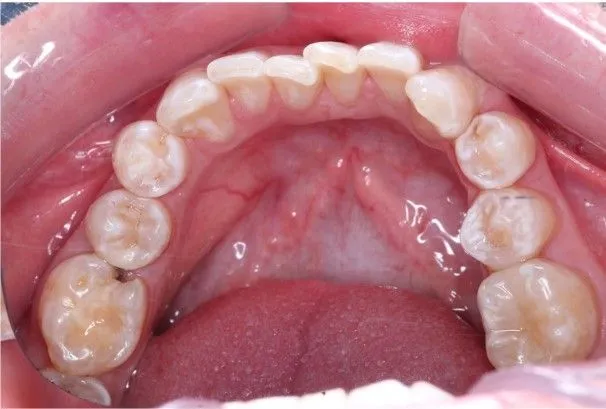

Пациент обратился с острой болью на нижней челюсти справа. В ходе осмотра было выявлено кариозное поражение зуба 4.5 сообщающаяся с полостью зуба и вторичное кариозное поражение зуба 4.6.

Проведена эндодонтическое лечение 4.6 с реставрация зуба и реставрация зуба 4.5.